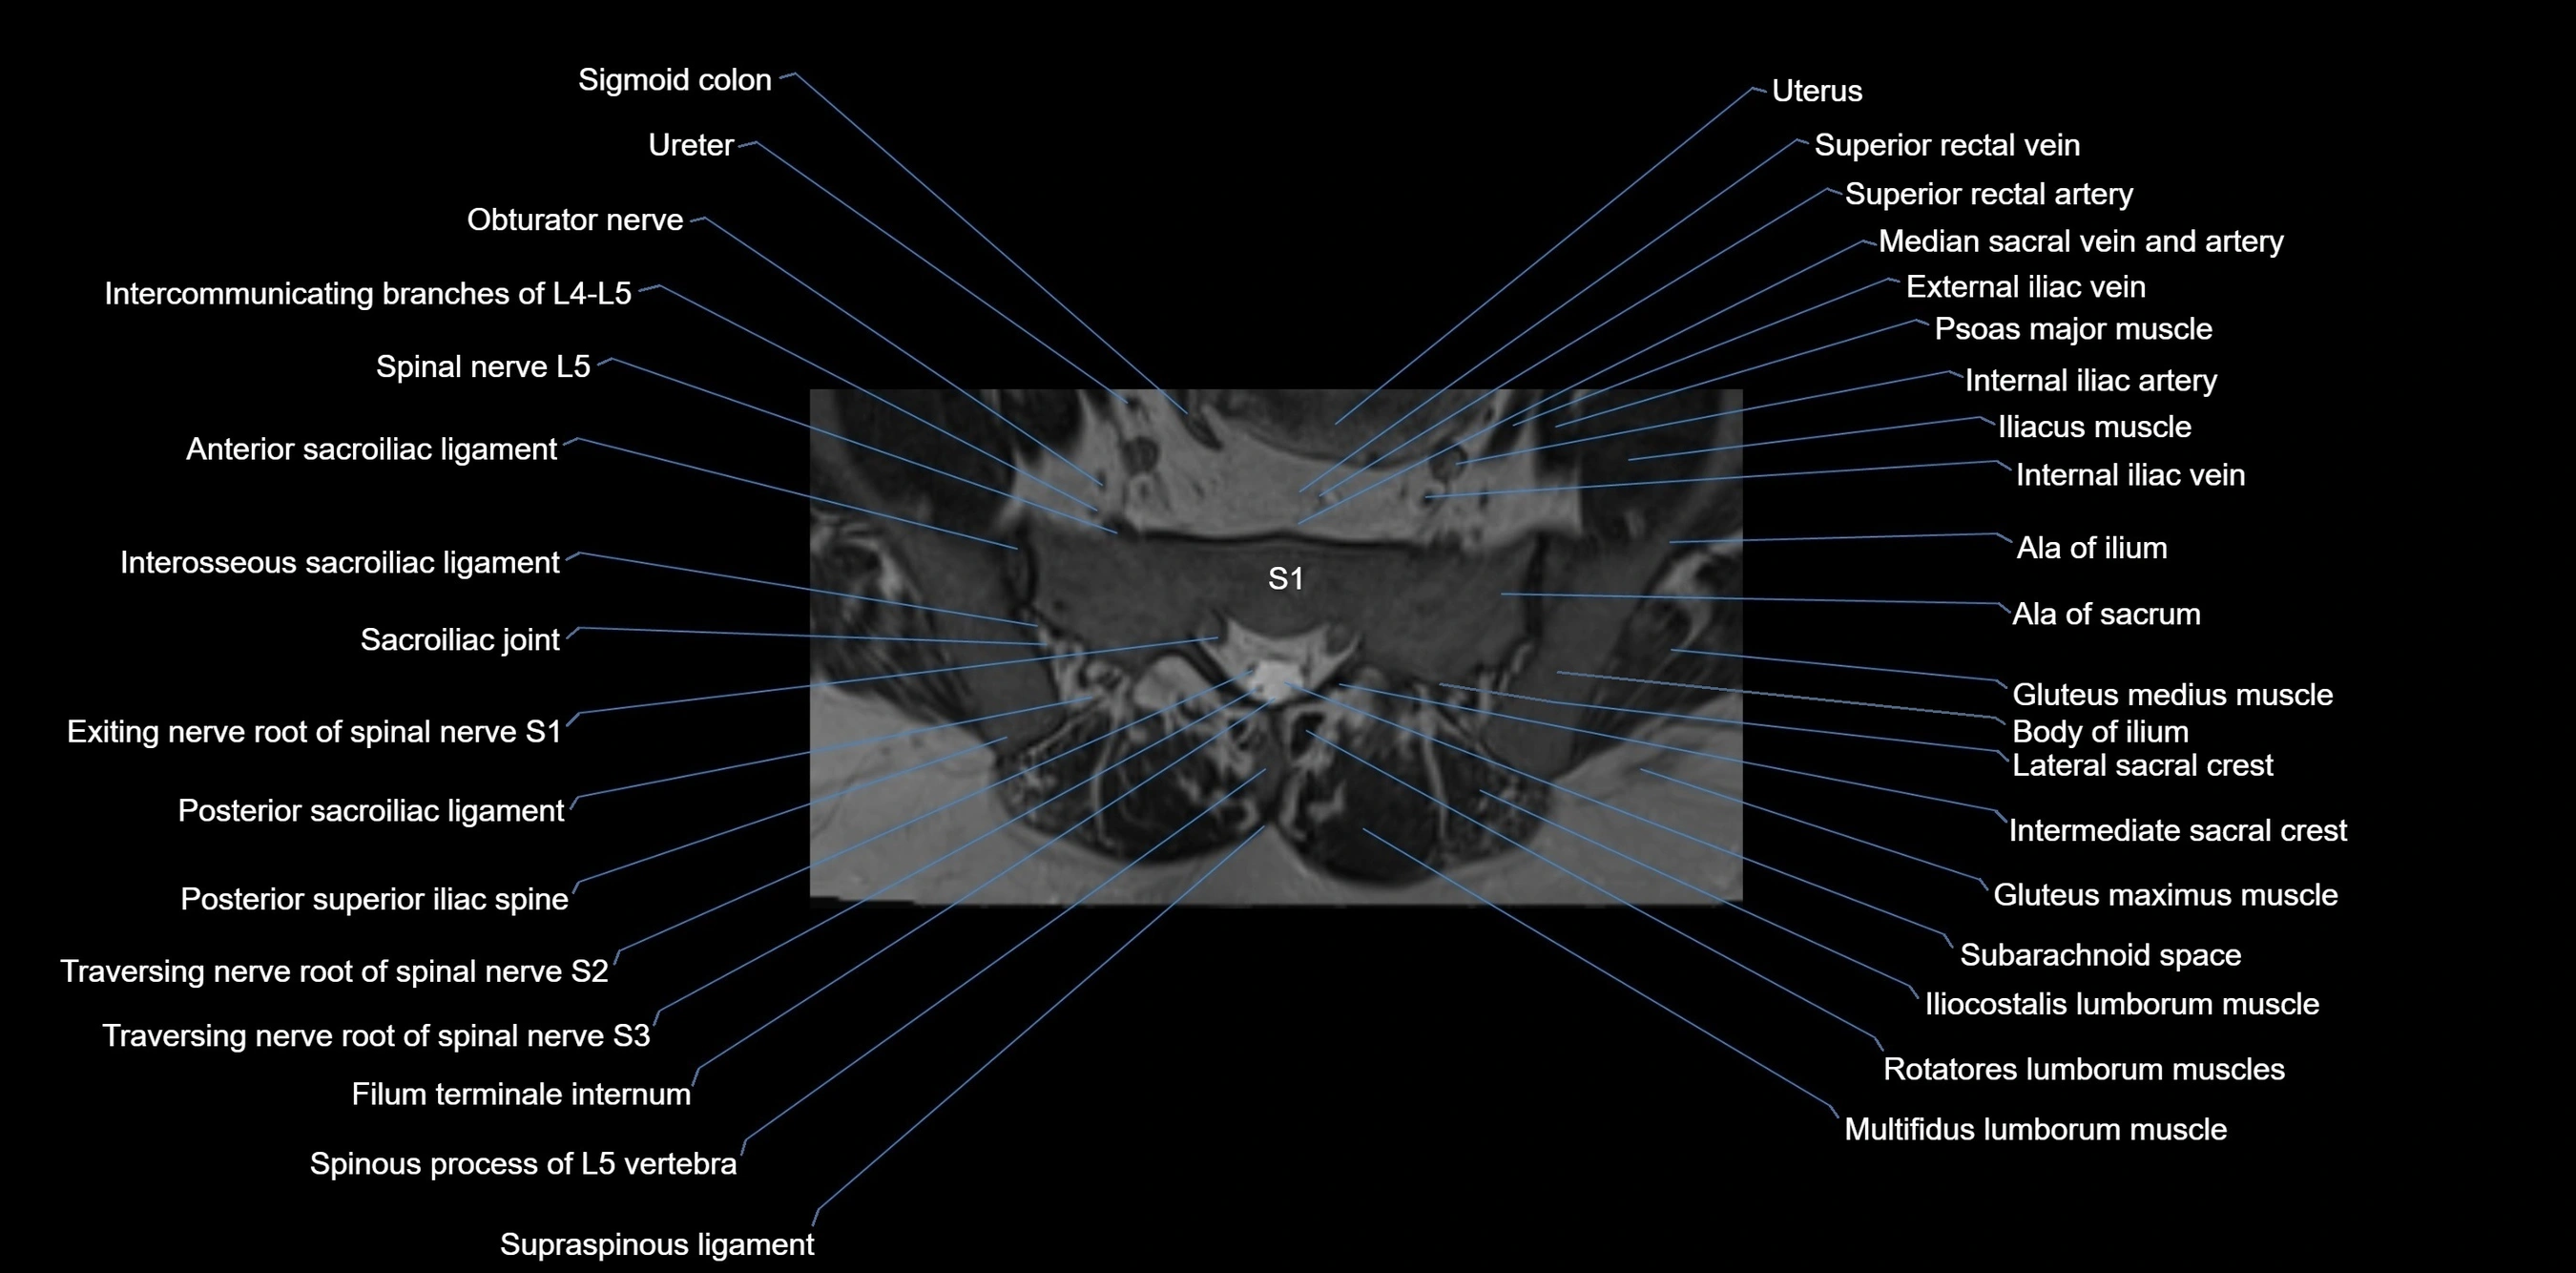

MRI Appearance

T1-weighted images:

• Cortical bone appears very low signal (dark); marrow shows intermediate signal

• Iliac fossa fat is bright against low-signal cortex

T2-weighted images:

• Cortical bone remains dark

• Marrow signal varies depending on fat content; edema or tumor shows hyperintensity

STIR:

• Suppresses fat, making bone marrow edema, fractures, or infiltrative lesions appear bright

• Excellent for trauma, sacroiliitis, and metastatic evaluation

T1 Fat-Saturated (Pre-contrast):

• Marrow: intermediate signal, fat suppressed

• Useful for detecting subtle marrow abnormalities adjacent to iliac cortex

T1 Fat-Saturated Post-Contrast (Gadolinium):

• Enhances vascularized structures, marrow pathology, tumors, and inflammatory changes

• Highlights soft tissue or bone invasion in pelvic neoplasms

MRI Non-Contrast 3D Imaging:

• Provides 3D morphology of iliac wing, crest, and articulations

• Used in preoperative planning for pelvic surgery and trauma reconstruction

MRI image

image